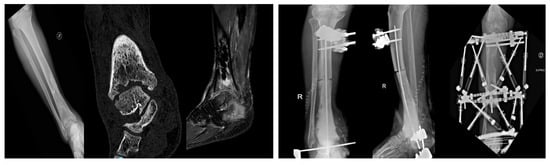

In 13 patients (76.4%), a polymethylmethacrylate (PMMA) spacer loaded with antibiotics was implanted. These spacers allowed for temporary defect filling, maintenance of soft tissue tension, and creation of a biologically active membrane consistent with the induced membrane technique, also known as the Masquelet technique. Six patients (35.3%) underwent bone resection exceeding 5 cm, with one patient requiring removal of a 15 cm segment of the tibial diaphysis. In all these cases, the Masquelet technique was applied to promote membrane formation prior to delayed reconstruction. One patient with massive segmental loss underwent reconstruction using a vascularized fibular graft in combination with circular external fixation, demonstrating the utility of advanced orthoplastic techniques in high-demand cases (Figure 1).

Figure 1.

30-year-old male with chronic osteomyelitis of the mid-distal tibia following an undiagnosed and untreated closed trauma for nearly two years. Management included a staged orthoplastic approach: (i) first stage—tibial resection (15 cm) with talar resection, Masquelet technique, and external fixation; (ii) second stage—removal of cement and external fixator with initiation of bone transport; (iii) third stage—fistulectomy, debridement, and reconstruction with a free vascularized fibular flap combined with circular external fixation. Radiographic and clinical signs of healing were achieved, with satisfactory pain control.